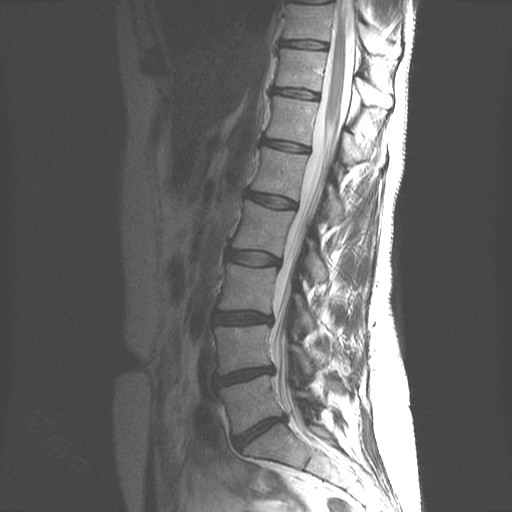

Lage Wervel Zuil